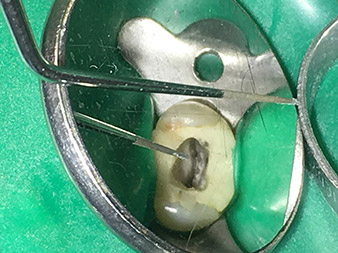

Dr. Nouraie: La punta con la que más me gusta trabajar es la punta 1E, que resulta especialmente idónea para activar el líquido de enjuague en el canal radicular. Gracias al diseño delgado de esta punta, con ella es posible llegar incluso a áreas profundas del canal y garantizar así una activación óptima.

Gracias a la transición reforzada con material desde el extremo de trabajo hasta el vástago, ha sido posible reducir a un mínimo el riesgo de que este delgado instrumento se rompa.

Dr. Nouraie: Tengo varias puntas preferidas. De todos modos, mi punta preferida absoluta y obligada es la punta 1E. Realmente puede utilizarse en cualquier tratamiento de los canales radiculares, puesto que con ella se activa el líquido de enjuague. Ya sabemos que, además de la preparación, el enjuague de los canales radiculares es el componente más importante del tratamiento. Un líquido de enjuague activado penetra de forma más profunda en los pequeños canales de dentina y, en consecuencia, logra mejores resultados. De este modo, la activación del líquido de enjuague desempeña un papel fundamental para mejorar la calidad de un tratamiento de este tipo.

Imagenes: Dr. Shahrad Nouraie Ashtiani, Bremen